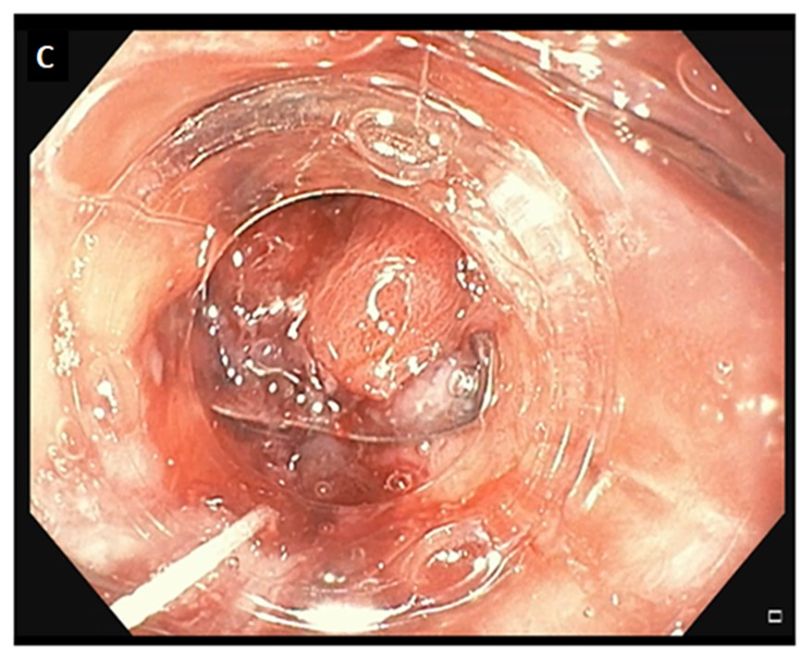

A 57-year-old male with a medical history of diabetes mellitus and morbid obesity underwent a Roux-en-Y gastric bypass surgery. The patient manifested a staple-line anastomotic leakage. After one week of conservative management, a 1.5cm persistent leakage was confirmed both radiologically (Figure A) and endoscopically (Figure B), so an endoscopic closure with over the scope clip (OTSC) using the suction method was performed (Figure C). Leakage of gastric liquids stopped after OTSC closure. No recurrence of the leakage was observed during the 12-month follow-up.

In conclusion, although various methods at treating leakages have been utilized, over-the-scope clip has recently gained growing interest with encouraging results in the management of early leaks after bariatric surgery.